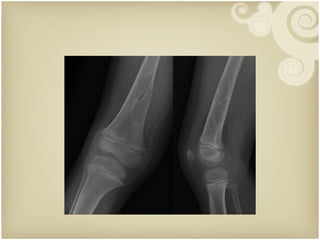

Radio-capitaller line Evaluation of paediatric elbow film

Supracondylar Fracture of Humerus Evaluation of paediatric elbow film

Radio-capitaller line Evaluationof paediatric elbow film

Supracondylar Fracture ofHumerus Evaluation of paediatric elbow film